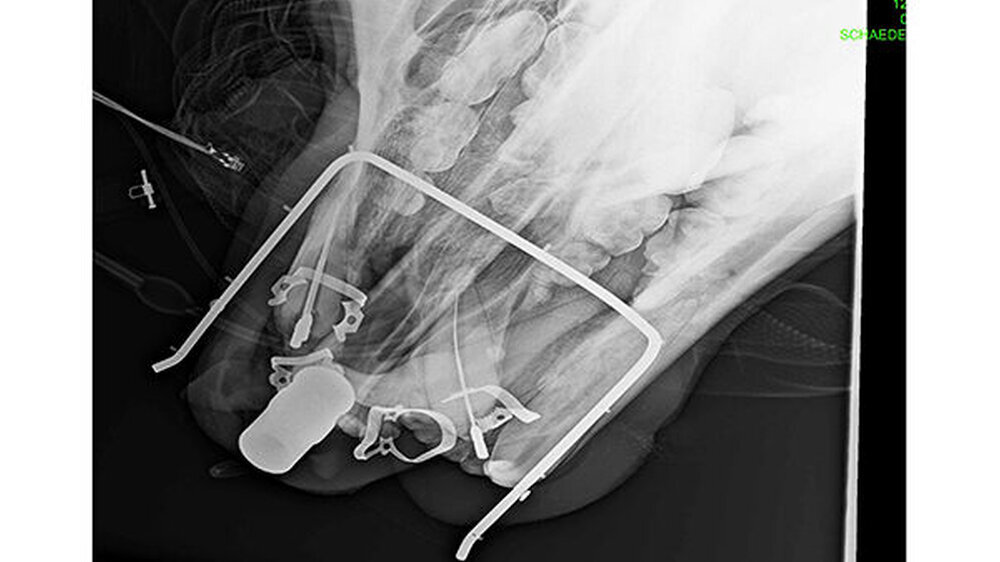

Die in den Bärenparks von Vier Pfoten lebenden Bären werden in regelmäßigen Abständen veterinärmedizinisch untersucht und behandelt. Sie werden aus ihren großen Freigehegen separiert oder direkt dort von den spezialisierten Veterinärmedizinern des Leibnitz Instituts für Zoo- und Wildtierforschung mit dem Narkosegewehr oder dem Blasrohr sediert. Das Team des jeweiligen Tierparks trägt den Bären in einen Behandlungsraum, wo alles für die Vollnarkose sowie für die zahnärztliche Behandlung vorbereitet ist. Die Veterinärmediziner verwenden eine für den Menschen sehr ähnliche i.V. Intubationsnarkose unter EKG-Kontrolle. Der Atemreflex wird allerdings nicht ausgeschaltet. Es werden Fell-, Blut-, Urin- und Stuhlproben entnommen, Röntgenaufnahmen unter anderen des Schädels sowie Ultraschallaufnahmen inklusive Doppleraufnahmen der Organe durchgeführt.

Die konservierenden Behandlungen werden mit Kofferdam durchgeführt. Wurzelkanalbehandlungen können aufgrund der Ausstattung eines Behandlungsraums eines Tierparks nicht mit dem OP-Mikroskop durchgeführt werden. Prothetische Versorgungen spielten bisher keine Rolle für mein Wildtier-Patientenklientel. Es gibt Braunbären, die fast zahnlos sind und dennoch feste Nahrung zerkleinern können.

Drittens: Wurzelkanalbehandlungen an den Fangzähnen, den Dentes Canini, bedeuten aufgrund der extremen Länge von 70 bis 80 Millimetern bei großem Kanallumen eine enorme Herausforderung. Sie erfordern einen hohen Aufwand bezüglich der Darstellung und des „Flarings“ des gekrümmten Kanallumens mit Lindemannfräsen (60 Millimeter) und langen Wurzelkanalfeilen (75 bis 90 Millimeter), um die notwendige Arbeitslänge zu erreichen. Die elektrometrische Längenbestimmung funktioniert bei diesen Dimensionen nicht wirklich präzise, so dass man ohne eine Röntgen-Mess-Aufnahme zu einer fehlerhaften Längenabstimmung kommt.

Besonders komplex ist die Obturation des Lumens entweder über die kombinierte laterale und vertikale Kondensation mittels spezieller Guttaperchaspitzen (60 Millimeter) und Sealer oder aber mittels MTA. Beide Techniken erforderten die Herstellung spezieller Instrumente. Der Verschluss erfolgte in den letzten 10 Jahren mittels eines autopolymerisierenden Aufbaumaterials inklusive Glasfaserstiften und einer Deckfüllung aus einem hochwertigen Nanokomposit mit Schmelz-Ätz-Technik. Bei jährlichen Nachkontrollen sehen wir die Haltbarkeit bestätigt oder müssen nur kleinere Füllungsreparaturen durchführen.